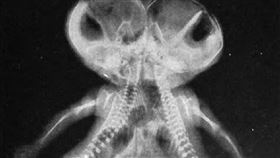

連體嬰結婚後能生小孩嗎?他們生了21子

連體嬰兒是一種罕見的情況,在以前科學還不是那麼進步的...